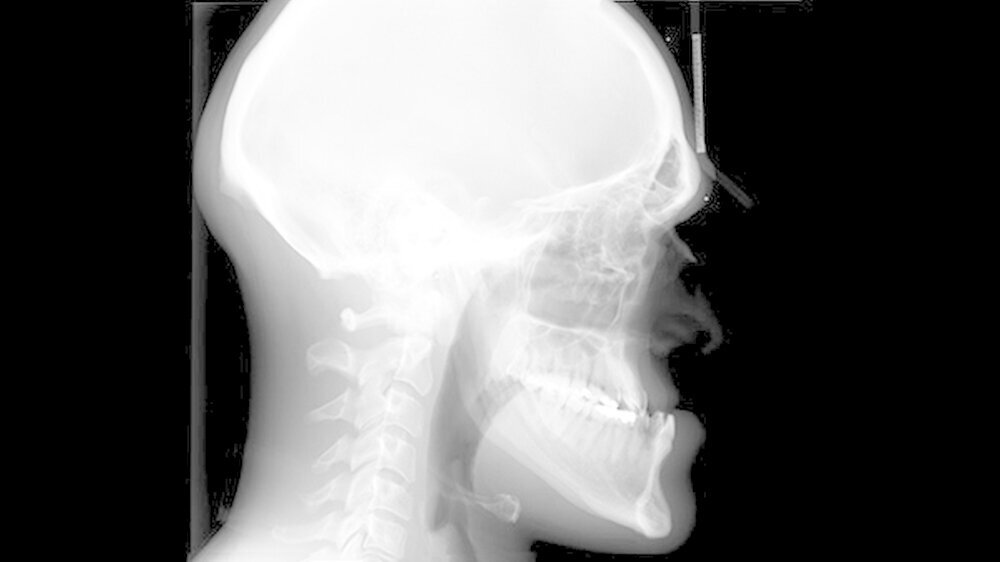

Hintergrund: Die Akromegalie ist eine endokrinologische Erkrankung, die durch eine Überproduktion des Wachstumshormons Somatropin hervorgerufen wird. Ein Hormon-produzierendes Adenom - das ist ein gutartiger Tumor - an der Hypophyse ist in den meisten Fällen die Ursache dieser Erkrankung.

Am Gesichtsschädel führen die Wachstumshormone zu einem persistierenden Wachstum des Unterkiefers. Die Körperproportionen erscheinen dadurch extrem unharmonisch und vergröbert. Der daraus entstehende Fehlbiss ist häufig auch verantwortlich für degenerative Kiefergelenkserkrankungen.